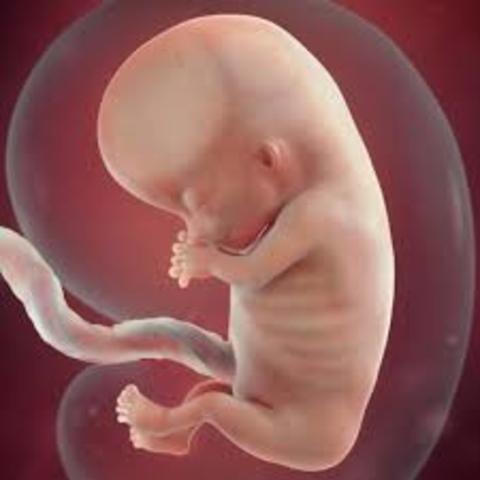

• semana 9 de embarazo

semana 9 de embarazo

Primeros movimientos (pero no te impacientes, todavía no los percibirás)

Son muchos los cambios que se producen el pequeño semana a semana. En la semana 9 de embarazo los párpados del bebé ya se han formado pero están fusionados. Se abrirán alrededor de las 26 semanas. Las costillas están creciendo en torno a los delicados órganos internos. Aparecen las rodillas y los codos. Los brazos, piernas y dedos se ven mejor.